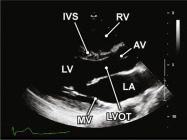

| 2.2. Mặt cắt trục dài cạnh ức khu trú vào thất trái

Cửa sổ siêu âm cạnh ức

Mặt cắt trục dài cạnh ức Đầu dò đặt tại bờ trái xương ức với marker hướng lên vai phải của bệnh nhân. Chùm siêu âm đặt vuông góc với thất trái. |

Nhĩ trái (LA)

Van hai lá (MV) Thất trái (LV) Đường ra thất trái (LVOT) Van động mạch chủ (AV) Vách liên thất (IVS) Thất phải (RV) |